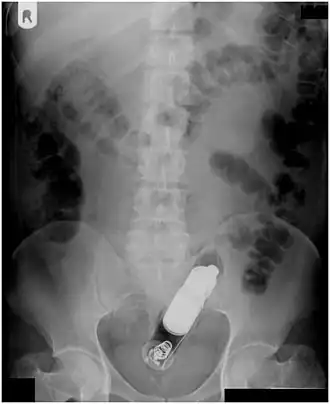

Abdominal X-ray showing small packages of cocaine swallowed by a trafficker. -